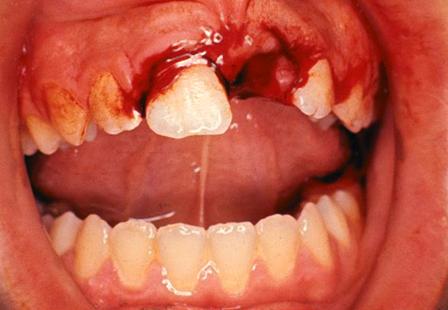

A dental extraction, which is often referred to as getting a tooth pulled, is a common procedure performed by pediatric dentists. Extractions may be necessary due to extensive dental cavities causing pain or infection, dental trauma or for orthodontic reasons. Most extractions are easy and routine and can be performed within the comfort and familiarity of our office. If Dr. Bennett feels that the extraction is more complicated, your child may be referred to an Oral Surgeon. To ensure that your child has a pleasant experience we recommend both Nitrous Oxide (to help them relax) and a local anesthetic (to numb the area). Rarely will your child require stitches. The area will heal on its own. It is important that you monitor your child so that they do not bite their lip or tongue. If there is sustained bleeding at home, try placing cotton gauze over the extraction site and have your child bite firmly for 30 minutes. You may also wet a tea bag and have your child bite on it gently. The tannic acid will stop bleeding naturally within 15 minutes. Have your child keep their fingers out of their mouth. Your child may eat a soft diet as soon as the numbness wears off, avoiding acidic food and drinks, such as tomato sauce and orange juice. Do not drink from a straw for the first 48 hours. Brush the area carefully and gently. Your child should relax after surgery, as strenuous physical activity may increase bleeding. You may start rinsing with a warm salt-water solution after 24 hours. Make your own salt water by mixing 1 tsp (5 g) of salt in a medium-sized glass [8 fl oz (237 mL)] of warm water. Give your child Tylenol or Motrin as per label instructions to control any discomfort they may experience. If you have any concerns about pain, bleeding or healing, contact us immediately.

Unfortunately, children sustain a fair amount of dental and facial trauma from sports-related injuries, falls and other accidents. The most important thing you can do as a parent is remain calm. If your child knocked out a permanent tooth, timely management is key to maintaining the life of the tooth. Depending on the nature and severity of the trauma, we may be able to effectively treat the traumatic injury in our office or even advise you on the at-home management over the phone (for less severe injuries) until you can make it in to our office. If your child has suffered a true medical emergency that involves more than just the mouth and peri-oral structures, call 911 or bring your child to the Emergency Room of your local hospital.

Reinserting an Avulsed (Knocked out) Permanent Tooth:

1) Find the tooth and do your best to hold it by the crown rather than the root.

2) You may gently rinse the tooth with saline or milk to remove any debris, being careful to only touch the crown of the tooth.

3) NOTE: Do not rinse the tooth with water.

4) If the entire root is still intact, try to reinsert it in the socket. If that is not possible, put the tooth in a glass of milk and take your child and the glass immediately to your pediatric dentist. Please note that baby teeth are generally not reinserted into the socket due to the risk of damage to the developing permanent tooth beneath it, however your child should still be seen by your pediatric dentist promptly.